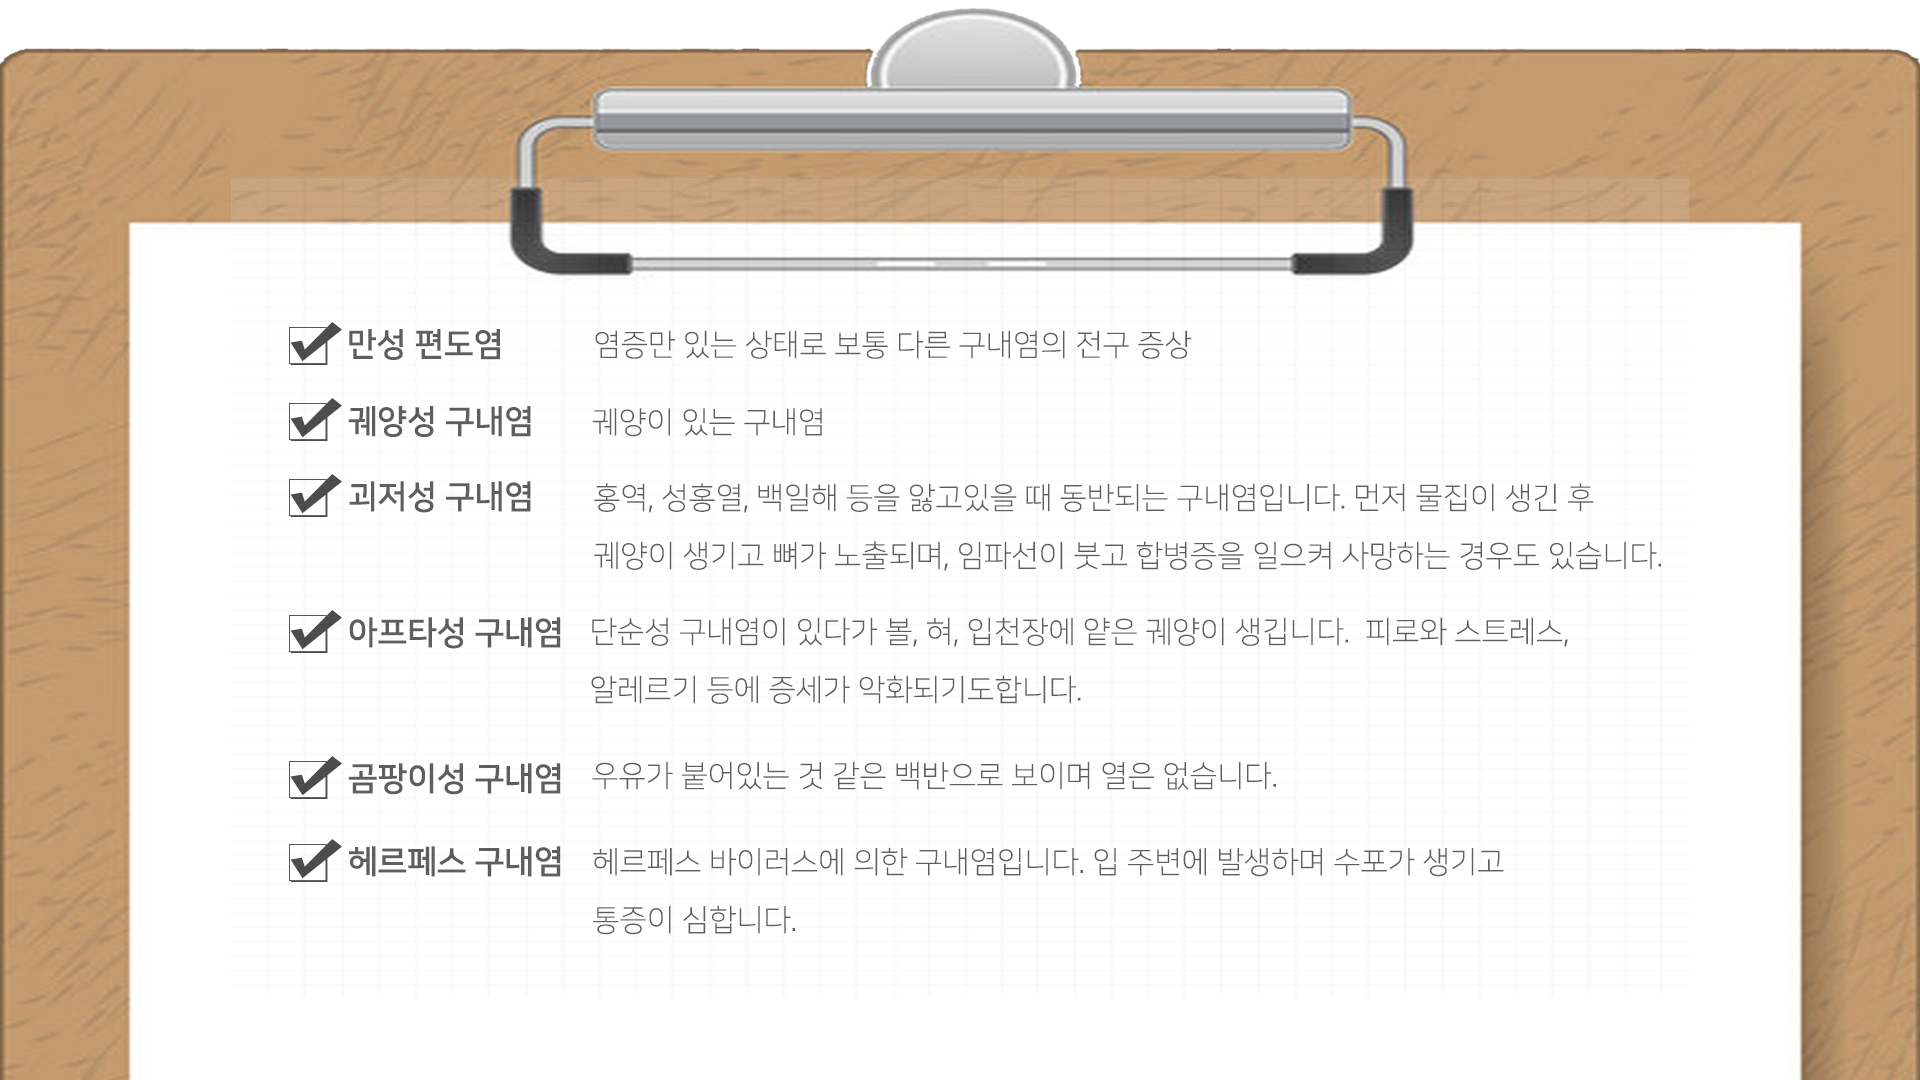

구내염이란 원인균이 알려진 감염에 의하거나 또는 비감염성 원인에 의해 입 안 점막(치아 주위 잇몸, 볼이나 입술 안쪽 점막, 입천정의 구개점막, 혀와 주변 점막)에 염증이 생기는 질환을 말합니다. 원인 요소를 기준으로 세균 감염, 바이러스 감염이 원인인 단순포진(헤르페스 구내염), 진균(곰팡이균)감염이 원인인 구강 캔디다증 등의 감염성 구강점막 질환과 자가면역이나 알레르기 반응에 인한 것으로 알려진 재발성 아프타성 구내궤양, 편평태선, 유천포창, 천포창 등의 비감염성 구강점막 질환으로 나눌 수 있습니다.

각 질환의 원인에 따라 항바이러스제, 항진균제, 항생제, 부신피질호르몬제, 면역억제제 등의 약물치료와 함께 구강위생 및 영양개선, 스트레스 경감 등 보조적인 요법을 적용합니다. 최근에는 레이저도 구강점막질환 치료에 많이 활용됩니다.

헤르페스성 구내염

국소마취 연고제를 사용하여 통증을 완화하거나 항바이러스제를 사용할 수 있습니다.

칸디다성 구내염

항진균제를 복용하는 것이 도움이 되며, 구강 청결을 유지하는 것이 중요합니다. 틀니 세척을 철저히 하고, 수면 시에는 틀니를 빼야 합니다.

재발성 아프타성 구내궤양

대게 1~2주 이내에 자연적으로 치유되며, 연고제나 항균세정제를 사용하면 일시적으로 도움이 됩니다. 심한 경우에는 스테로이드 제제를 사용하기도 합니다.